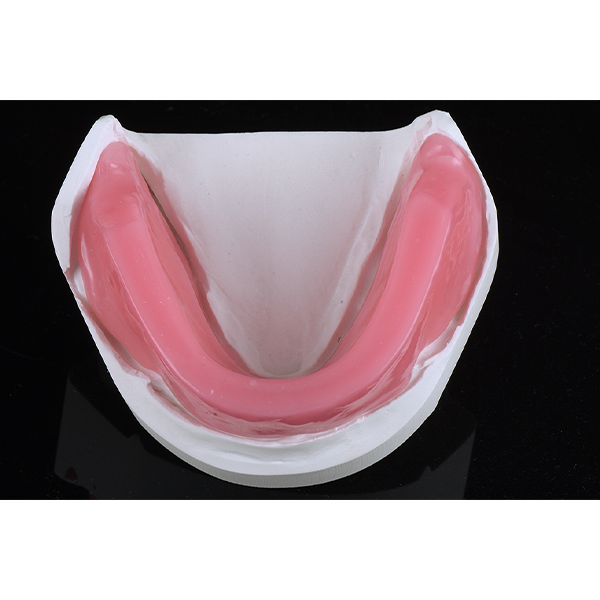

Après la mise en moufle et l'ébouillantage, les dents ont été repositionnées, conditionnées et des caractérisations blanchâtres, pourpres, orange clair, bleues et roses ont d'abord été réalisées au niveau du le bouclier labial. La base a ensuite été incrustée de résines pour prothèses de couleurs orange-rouge, rouge foncé, rouge clair, rose et rose foncé, et tous les polymères à chaud ont été pressés en une seule fois. Après le stockage sous pression, les prothèses finies ont été démouflées, finies et polies. La stratification anatomique tridimensionnelle de VITAPAN EXCELL en masse d'émail, de collet et de dentine avait un aspect absolument naturel dans l'anatomie muco-gingivale reproduite de la base prothétique. Le patient a pu s'habituer rapidement à sa nouvelle prothèse, notamment grâce à l'effet esthétique réussi. Après une courte phase d'adaptation et des corrections minimes dans l'environnement biodynamique, il s'est très bien débrouillé avec sa première restauration prothétique amovible complète et en était pleinement satisfait.